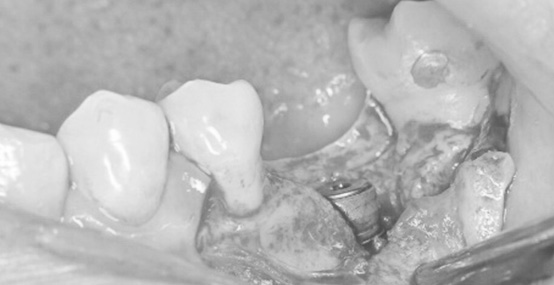

患者さまは「奥歯の歯ぐきが腫れている」「咬むと違和感がある」とのことで来院されました。

検査を行ったところ、奥歯には強い負担がかかっており、歯の根が折れてしまっている状態(歯根破折)でした。

残念ながらこの状態では歯を残すことが難しく、抜歯が必要でした。

この症例では

という問題がありました。

この状態でそのままインプラントを入れると

が起こる可能性があります。

当院では長く美しく機能するインプラント治療を患者さまに提供することを最も大切にしています。

そのため術前に徹底した診断と治療計画を立て

をすることで最終的な被せものの厚みを確保できる設計を行いました。

一次手術後(インプラント体埋入後の写真です)

術前の状態

術中:頬側の骨の不足している箇所に人工骨と吸収する膜を入れている写真です